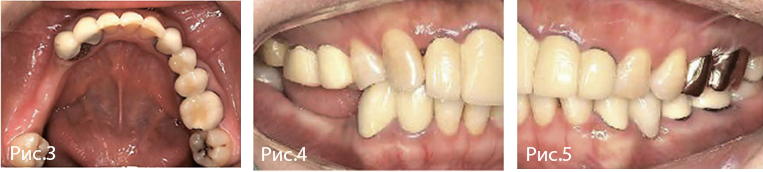

Рис. 1—2. Исходная рентгенологическая картина.

Рис. 3—5. Клиническая картина.